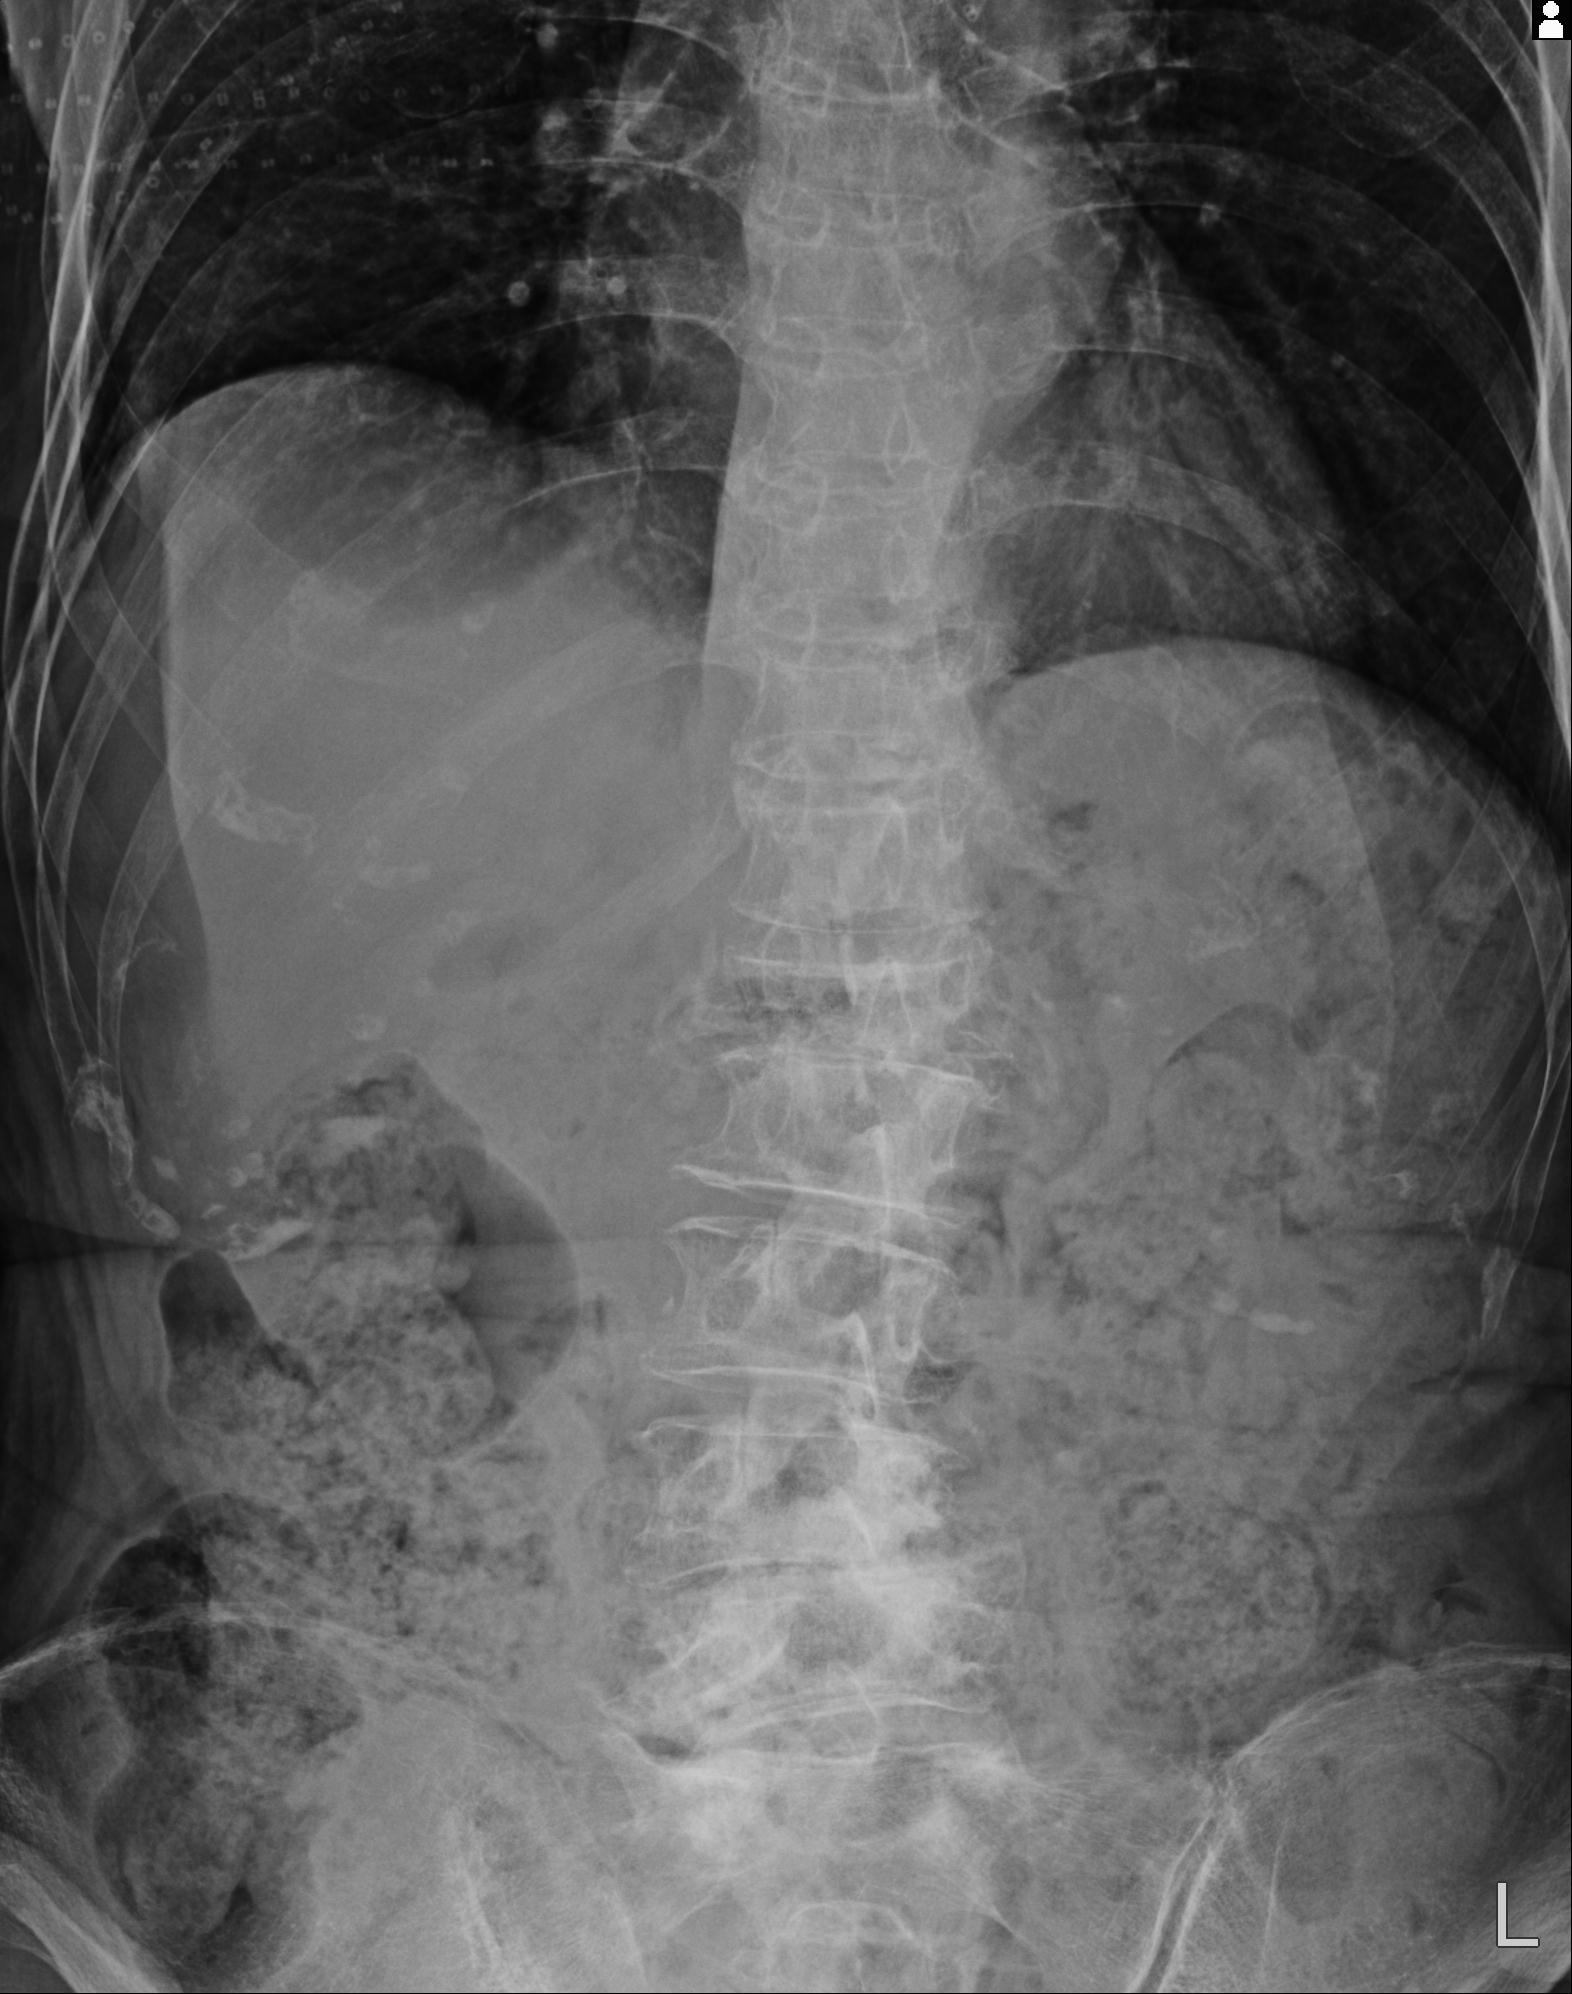

102916 2/1 と 3/22 腰椎 2R 74歳女性 LIFX